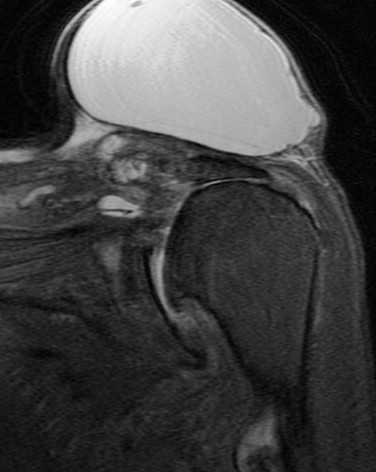

74 y/o female with mass on shoulder. Also pain. Evaluate mass and r/o rotator cuff tear.

Large cyst associated with a rotator cuff tear and AC arthrosis. Geyser phenomenon if communication shown at arthrography (some definitions specify arthrography). This was not an arthrogram. Patient also has a chronic rotator cuff tear. Reference article.

Large cyst above a degenerated acromioclavicular joint ( RID1895 )